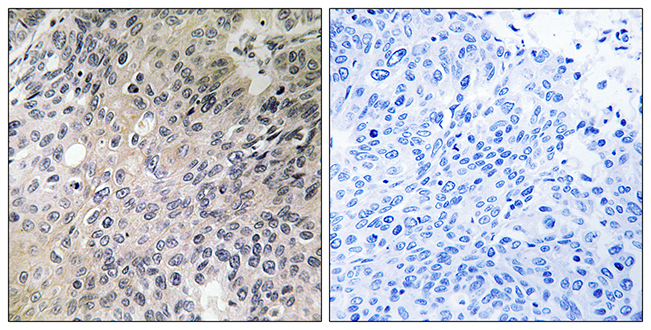

Anti-UCP2 AntibodyA97758

ApplicationsELISA, ImmunoHistoChemistry

ReactivityHuman, Mouse, Rat